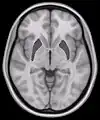

- Horizontal slice of MRI-image showing the putamen. The other nuclei of the basal ganglia (caudate nucleus and globus pallidus) can be seen as well.